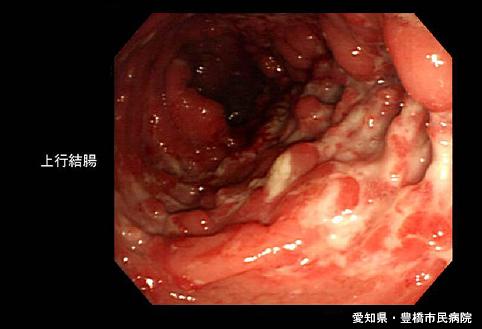

症例提示(所在地,施設名等): 愛知県・ 豊橋市民病院

疾患(病理主体)の分類炎症性・潰瘍性疾患/クローン病

部位(臓器別)大腸/上行

検査方法内視鏡

病変の最大径(ミリ)40以上